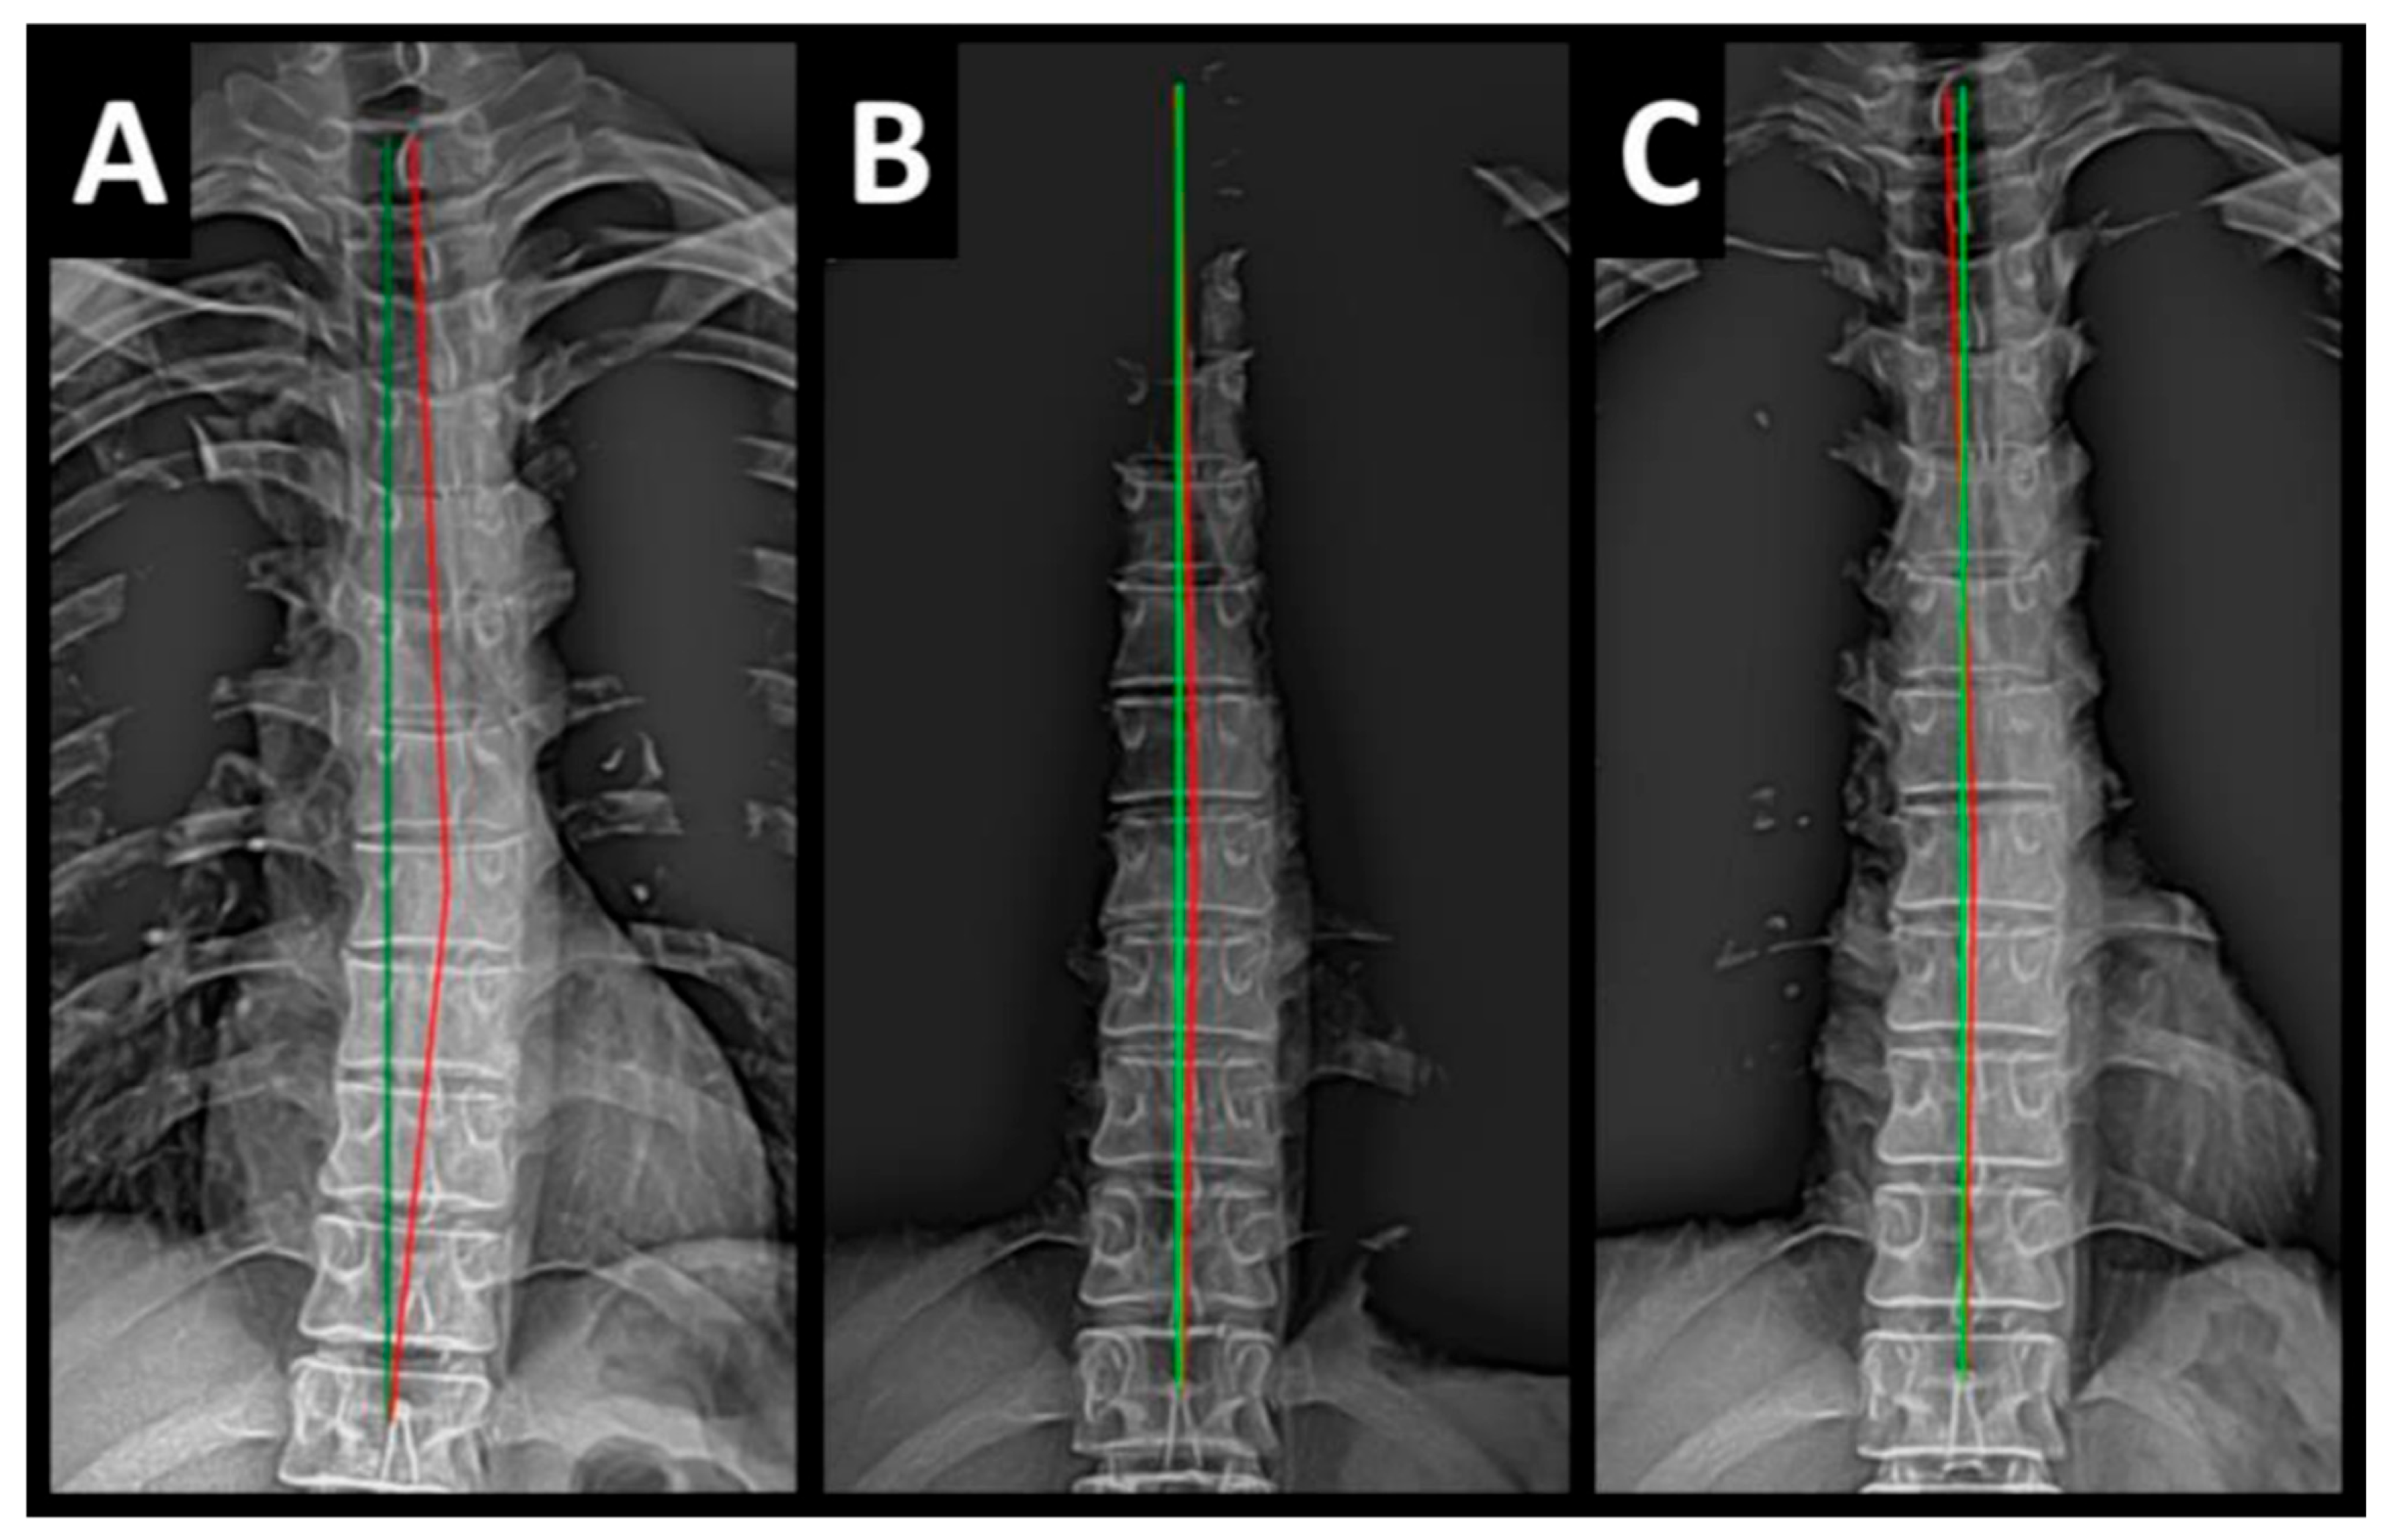

Radiography of the spine was performed with the patient upright in neutral position. Anterior–posterior (AP) and lateral films were assessed using PostureRay® digital radiographic mensuration software (Posture Co, Inc., Trinity, FL, USA) [14]. The program uses the Risser–Ferguson measurement for the AP views and the Harrison posterior tangent method (HPTM) of measurement for the lateral views. The program also compares the patient alignment of both segmental and global measurements to models of ideal spine parameters; prior studies have shown exceptionally high reliability using this system [15]. The sagittal spine absolute rotation angle (ARA) from the 2nd cervical vertebra to the 7th (ARAC2–C7) measured −18.1° (average is −34°, ideal is −42°, pain threshold is −20° [16]) (Figure 2, Figure 3, Figure 4 and Figure 5) and the AP cervical X-ray demonstrated a right lateral flexion angle relative to true vertical of the lower cervical and upper thoracic spine (cervicodorsal angle (CDA)) measuring 5.6° (ideal is 0° [16]) with a right translation of C2 with respect to T5 (TXC2–T5) measuring −17.2 mm (ideal is 0 mm). There was an increased mid-thoracic angle with a right-sided concavity from T1 to T12 (MTAT1–T12) of 9.1° (ideal is 0° [16]) with an increased translation at T8 apex of mid-thoracic angle with respect to T12 (+TXT8–T12) measuring 15.2 mm (ideal is 0 mm). There was a decreased sagittal curvature of the lumbar spine from L1 to L5 (ARAL1–L5) measuring −17.9° (ideal is −40°, average range is 35–45° [16]). The modified Ferguson pelvic radiograph demonstrated a sacral base unleveling in the frontal plane measuring −11.3 mm, being lower on the right. There was a lumbosacral angle from L1 to L5 with an L3 apex (LSA L1–L5) of −84.9° (ideal is 90°).

Post-treatment posture analysis showed improved posture (Figure 1A–C). Post-treatment radiographic examination revealed the following: improved ARAC2–C7 measuring −29.4° (vs. −18.1°); rotation around the z-axis of the thorax (RZT5) measured 1.8° (vs. normal 0°); improved -TxC2–T5 measuring −5.7 mm (vs. −17.2 mm); improved MTA T1–T12 measuring 2.1° (vs. 9.1°); improved +TxT8–T12 measuring 3.5 mm (vs. 15.2 mm); improved ARAL1–L5 measuring −25.1° (vs. −17.9°); improved sacral base unleveling in the frontal plane measuring −1.0 mm low on the left (vs. −11.3 mm low on the right); and improved LSA L1–L5 of −88.0° (vs. −84.9°) (Figure 2B, Figure 3B, Figure 4B and Figure 5B). Post-treatment RODI score was 12% (vs. 54%), indicating minimal disability. All post-treatment SF-36 scores showed improvements (Table 1). One-year follow-up posture analysis showed a maintenance of the improved posture. One-year follow-up radiographic examination revealed maintained sagittal balance and coronal spinal alignment correction improvements (Figure 2C, Figure 3C, Figure 4C and Figure 5C). One-year follow-up RODI score was 2% indicating minimal or resolved disability from baseline (54%). Post-treatment SF-36 scores showed maintained or further improved HRQoL measures reported by the patient. Long term follow-up found minimal forward head posture on the lateral posture photograph, a slight return to baseline on the A-P cervical radiograph with a right head translation measuring 7 mm. Lateral cervical radiograph assessment at long-term found the lordosis to be well maintained at 34° ARA with minimal C2-vertical anterior head translation of 6 mm. lateral lumbar radiograph showed a slight loss of lordosis at follow-up of 19°. All subjective initial symptoms were reported to be resolved at long-term follow-up. Long term follow-up SF-36 scores were the same as post-treatment with the exception of vitality, which was slightly improved (Table 1). There were no positive orthopedic or neurological tests at follow-up. The patient continued to use the ProLordotic neck exerciser at home 1–3 times per week for up to 10 min (Figure 7).

Figure 4. (AC) Pre-treatment, post-treatment, and 1-year follow-up AP thoracic radiographs. Image Features: The green line represents a normal, ideal frontal thoracic spinal alignment. The red line represents the actual frontal alignment of the T1–T12 vertebrae. The right side of the radiographs are the left side of the patient.